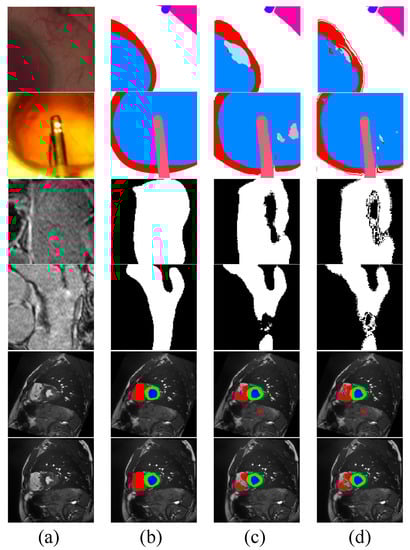

4.2. Results on CaDIS

4.3. Results on Late Gadolinium Enhancement MRI

4.4. Results on ACDC